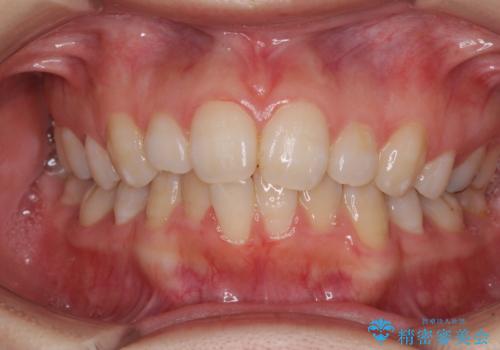

前歯をさげたい 歯を抜かずに マウスピース矯正で治したい

[ インビザライン矯正 ]マイクロインプラント用いた大きな遠心移動

担当医 大元洋佑